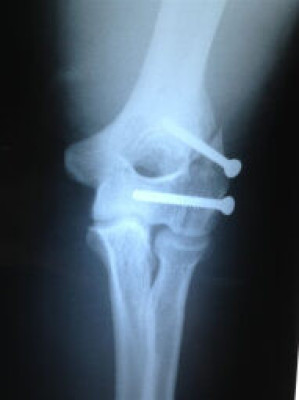

Fractura de Codo - Después